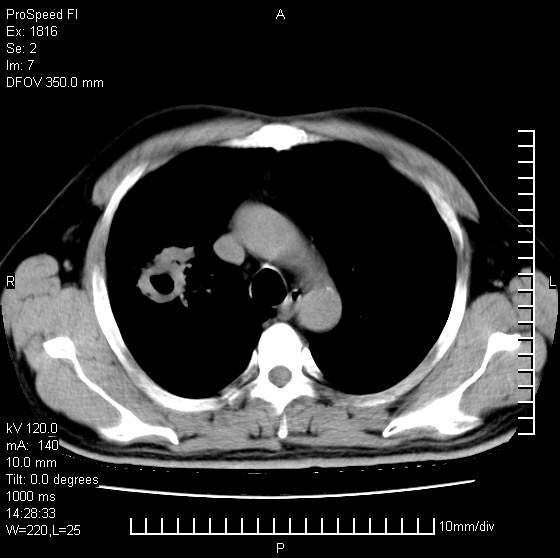

男性,50 ,肺结核9年,咳嗽,胸痛一周。右上肺见一厚壁空洞,周边有点样钙化,胸膜牵拉,洞壁较光整。诊断结核性空洞。有癌性的可能吗? 余肺野无异常,没有上传。

结核有可能,肺癌待排。空洞的前上还方见一软组织结节影。

部分层面见空洞为近似新月形,洞壁内缘尚规整且近肺门侧,周围见索条影、卫星灶,结合病史,首先考虑肺tb可能大。

右肺上叶为两个病灶,前面为陈旧型结核灶,其后方病灶像肺脓肿

9年的结核应该呈现多形态病灶,该病例只能见到少许纤维索条影,似乎与结核的演变不太相符。空洞内壁不光整,外侧伴有胸膜粘连,考虑癌性空洞可能性大,期待结果。